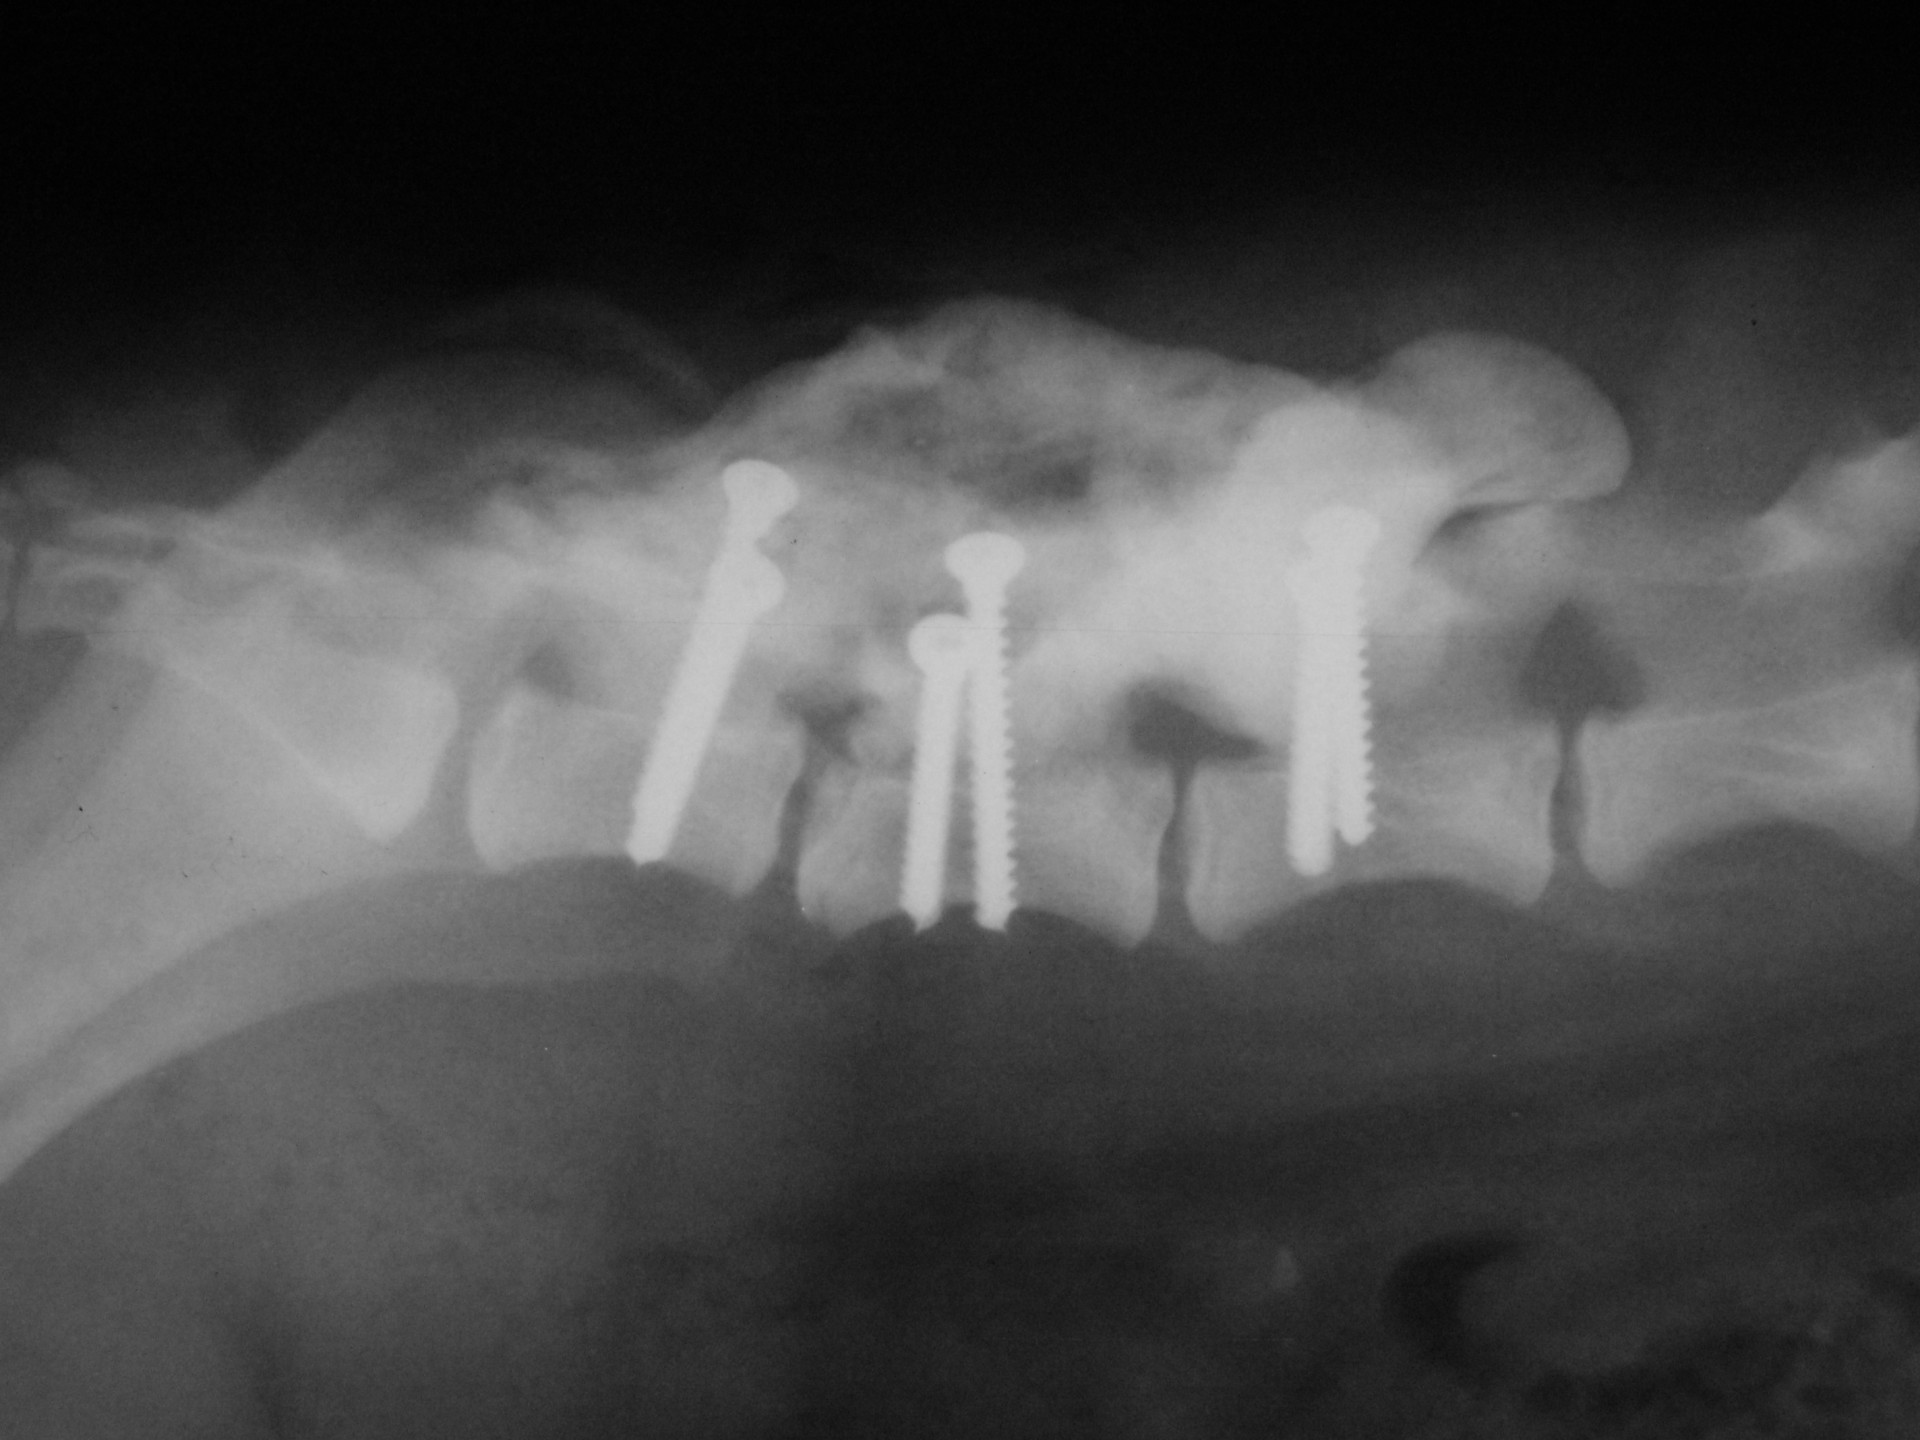

A törött csigolyatestek adaptációja és rögzítése a nyitott gerinccsatorna mellett komoly kihívást jelent. A későbbi elmozdulás elkerülésére többféle műtéttechnika alkalmazható, melyek közül a csigolyatestek lemezes osteosynthesise ill a fixateur interna használata terjedt el leginkább. Első esetben a sérülés előtti és mögötti csigolyákat lemez és csavarok segítségével egymáshoz rögzítjük, míg az utóbbi esetben a törés előtti és mögötti egy vagy több csigolyatestet két oldalról behelyezett csavarok és egy steril kétkomponensű akrilát műgyanta segítségével rögzítjük.

Bármilyen műtét után kialakulhat olyan szövődmény, mely gennykeltő baktériumok műtéti sebben történő elszaporodásával jár (szeptikus szövődmény). Különösen igaz ez olyan beavatkozásokra, amikor valamilyen idegen anyag (implantatum) kerül a szervezetbe beültetésre. Ilyen idegen anyag a gerinctörés műtéteknél használatos fixateur interna rögzítőanyaga (akrilát műgyanta) is. Abban az esetben, amikor a szeptikus szövődmény antibiotikumok célzott adásával nem gyógyítható, a test számára idegen anyagot el kell távolítanunk. A gerinctörés műtéténél ez a nyitott gerinccsatorna miatt fokozott kockázatot jelent. Az implantatum eltávolítását követően azonban a szeptikus folyamat gyógyul és a helyén kialakuló kötőszövet a fixateur externának megfelelően rögzíti a gyógyulófélben lévő csigolyát is.